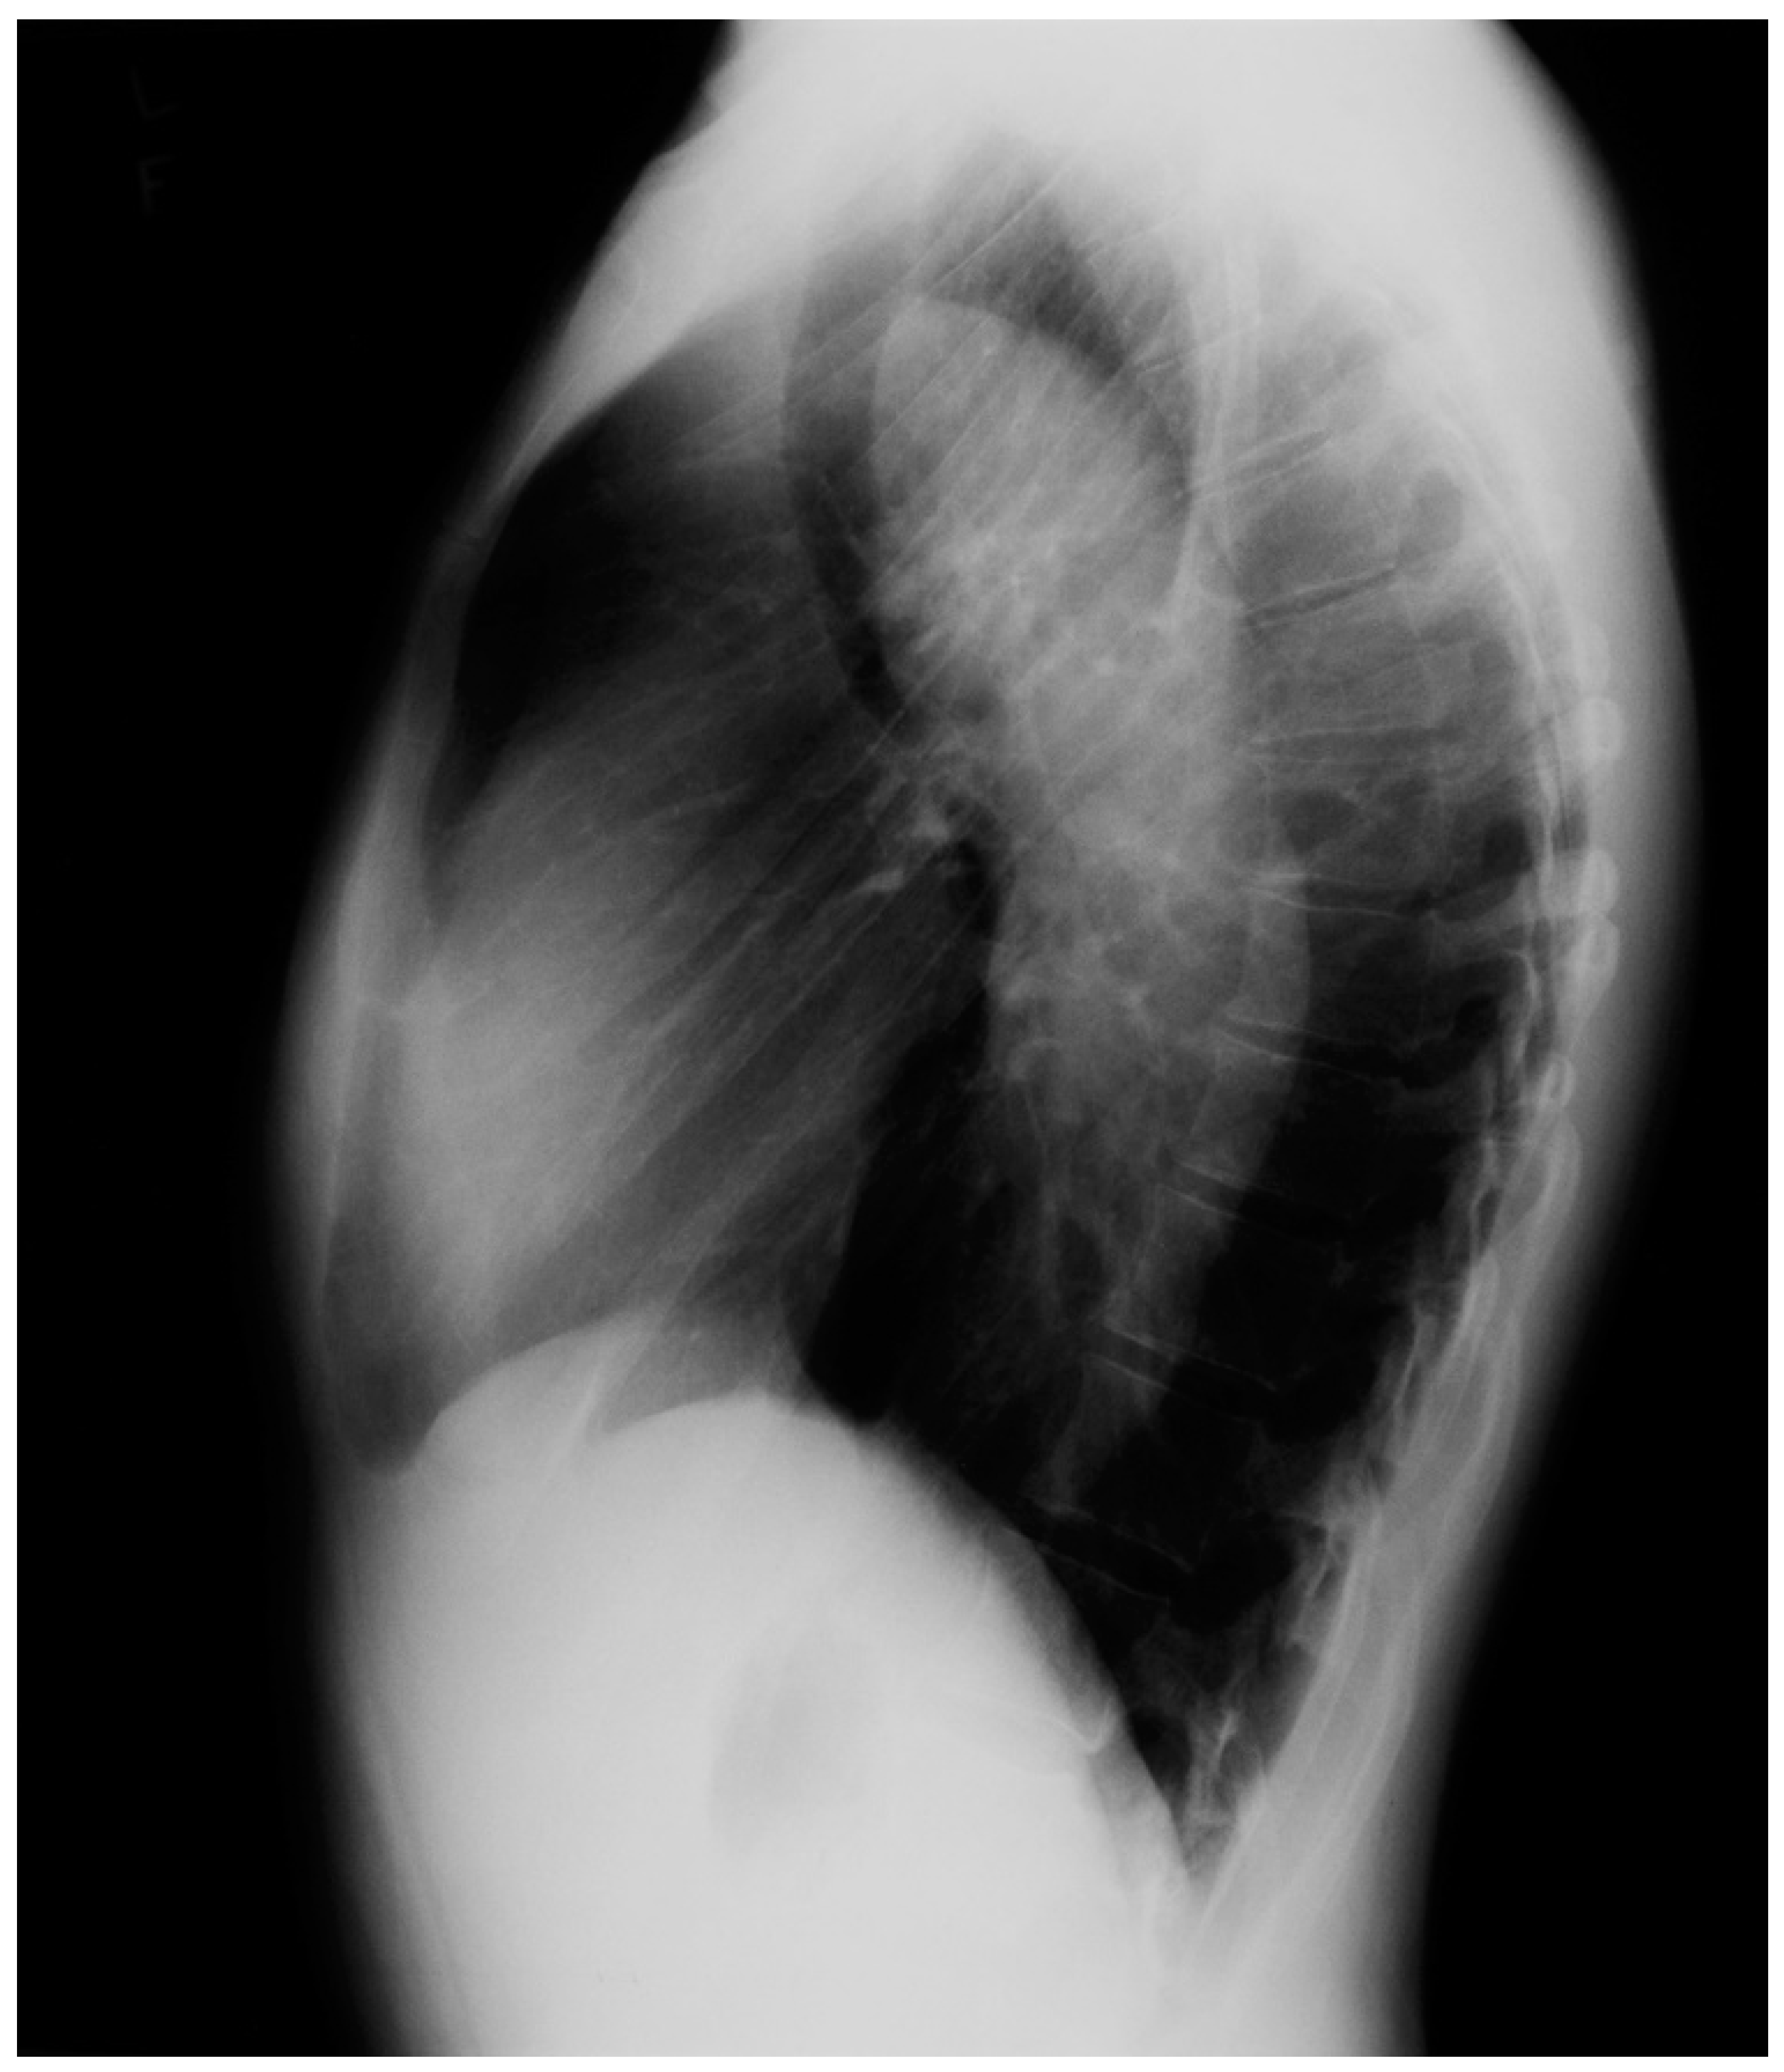

Figure 21.

Lateral chest X-ray of Marfan syndrome: this chest X-ray was done on the same 24-year-old female above. It shows the dorsal kyphosis and pectus carinatum (also known as pigeon chest). The ascending, arch, and descending aorta were markedly dilated. Additional imaging measured the minimum thoracic aortic diameter to be 6 cm. She went on to have a mechanical aortic valve replacement, followed by aortic root and ascending aortic replacement via median sternotomy, and then descending aortic replacement via left lateral thoracotomy. A few years later she required an extensive abdominal aortic replacement with multiple arterial anastomoses to vital organs supplied by the abdominal aorta. She was followed for 30 years after her first diagnosis of MFS and her first aortic operation and remained NYHA functional class 1–2. Suspicion of the diagnosis of MFS in an asymptomatic patient that leads to a CXR is an important first step in the optimal care of MFS.